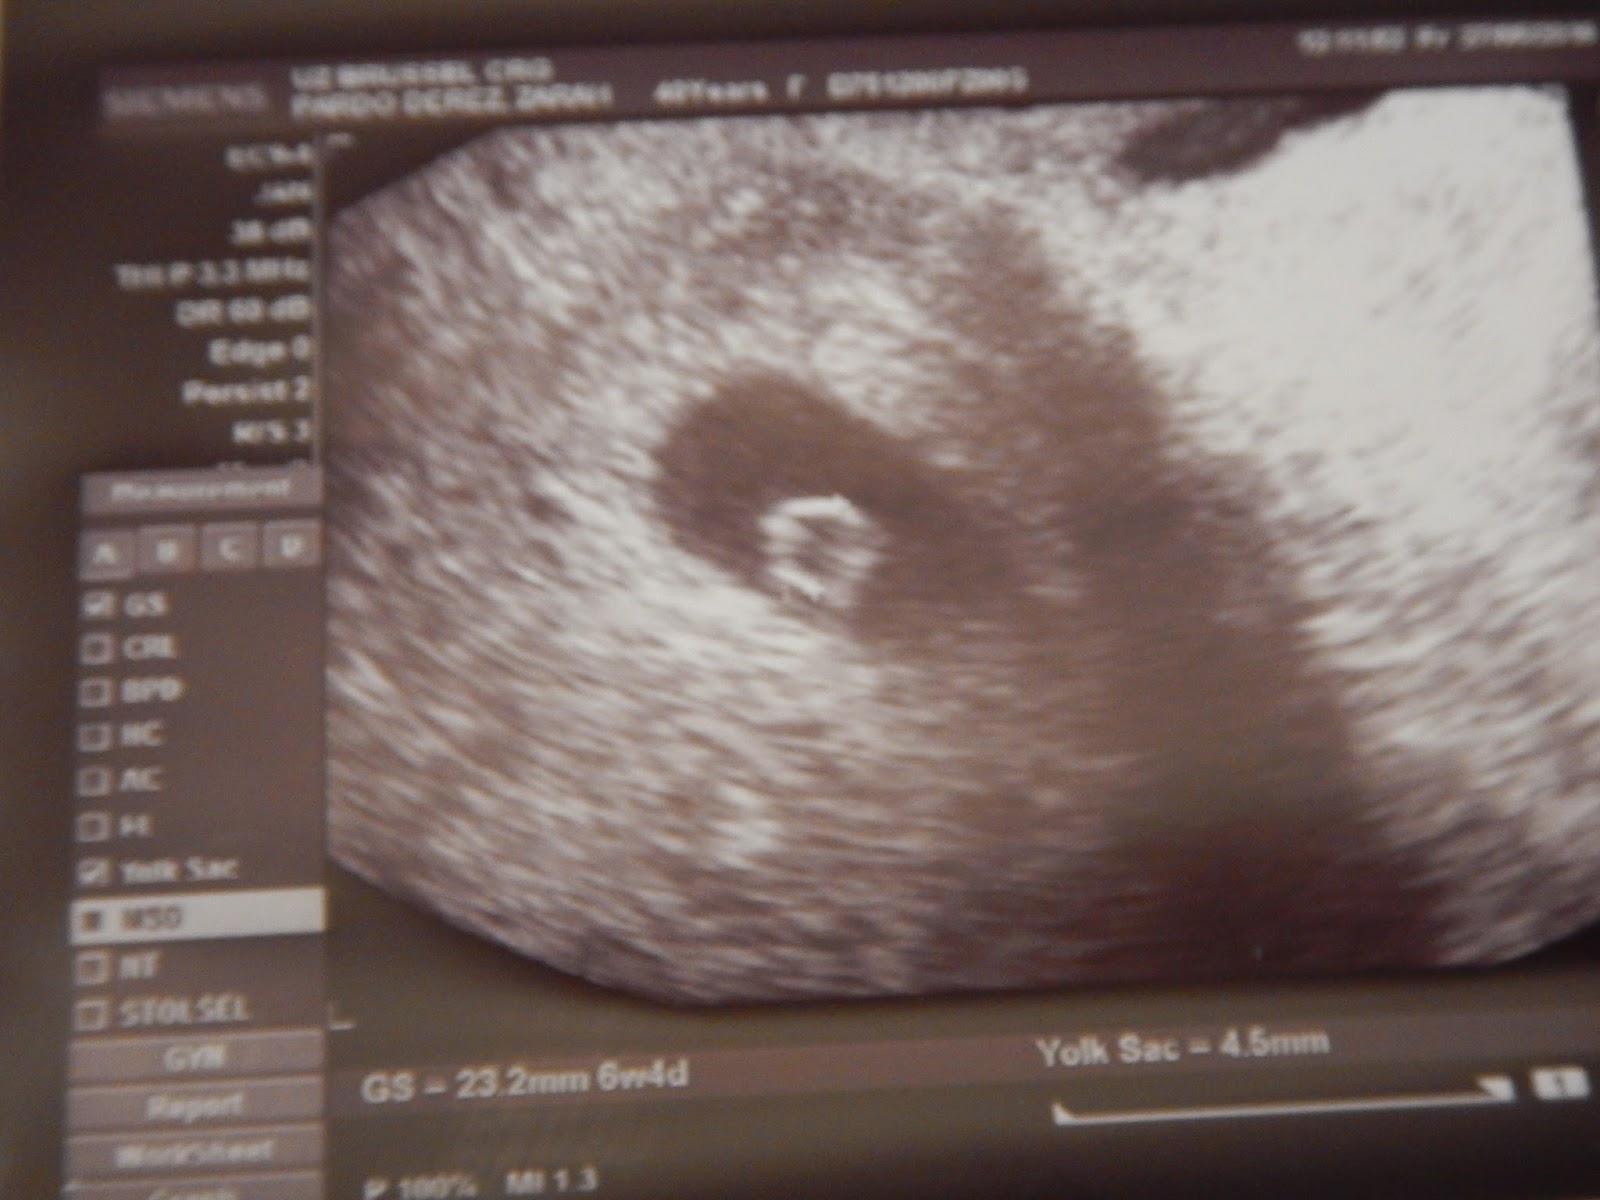

Ultrasound in early pregnancy (before 12 weeks) - Dating Scan Dating ultrasound A 'dating ultrasound' or 'dating scan' is a scan done early in pregnancy (before 12 weeks) . It is usually done to check how many weeks pregnant you are and therefore to calculate the estimated due date, but it can be done for other reasons . Only a few women need a dating scan .

A TVS , also known as an internal scan , is most commonly done to confirm that you are pregnant . It's more accurate and gives clearer images than an abdominal ultrasound in early pregnancy . A transvaginal scan can: Detect the presence of the sac and/or an embryo . Find out if you're carrying more than one baby as early as the fifth week of your pregnancy .

Sometimes a TVS is also done to date your pregnancy to be sure your due date is correct . After 10 weeks and for the rest of your pregnancy, you will have abdominal scans because once your uterus expands and moves up in your abdomen, your baby becomes more visible through your tummy .

The earlier in pregnancy a scan is performed, the more accurate the age assignment from crown-rump length . The initial age assignment should not be revised on subsequent scans 5 . Overall, the accuracy of sonographic dating in the first trimester is ~5 days (95% confidence range) .

Overall, the accuracy of sonographic dating in the first trimester is +/-5 days (95% confidence range) . Cardiac activity should be present in an embryo with a CRL β₯7 mm 3 . If it not detected at this size on transvaginal scanning performed by an experienced operator, it is an indicator of failed early pregnancy (missed miscarriage) .